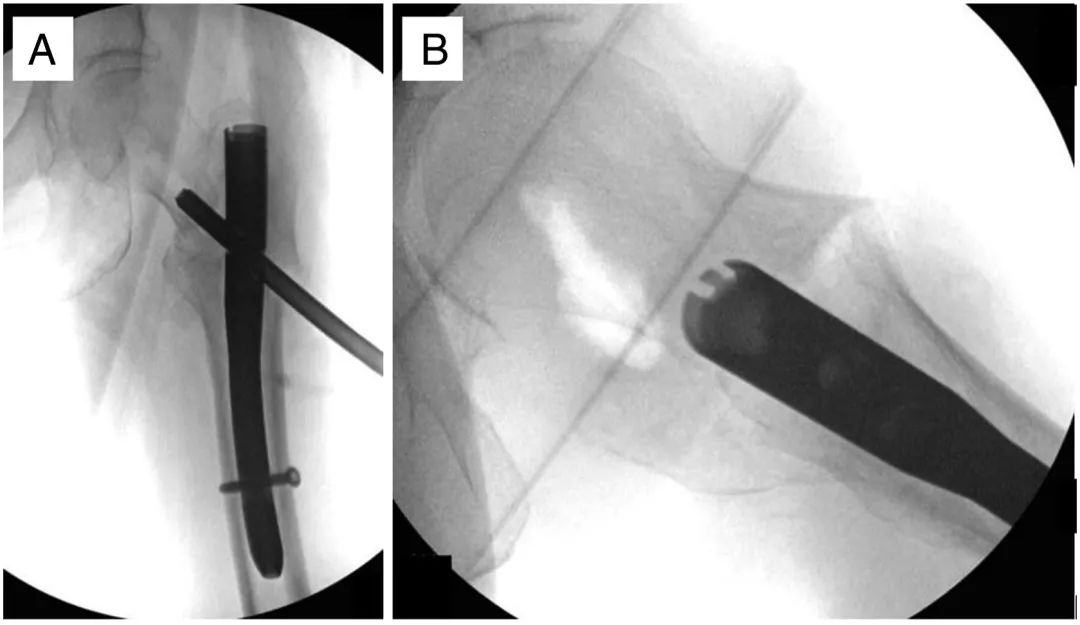

Затем делают поперечный разрез длиной 1-2 см вниз через подвздошно-большеберцовую фасцию (ITB).Оригинальный головной гвоздь удаляется с помощью направляющей с обратной резьбой (рис. 3).В случае перфорации головки бедренной кости используется полый направитель с дистальным блокирующим винтом, чтобы предотвратить просачивание цемента в сустав (рис. 3А).В частности, матрицу сначала вводили после удаления двух внешних слоев тройной канюли, а затем помещали в перфорированную область путем повторной установки двух внешних слоев.

Рисунок 3. Интраоперационные переднезаднее (А) и боковое (В) изображения другого пациента, демонстрирующие головку бедренной кости с трансплантатом интерстициального костного дефекта.